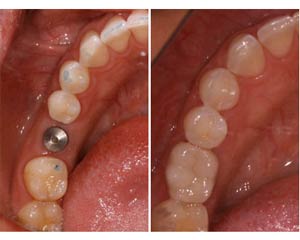

ایمپلنت